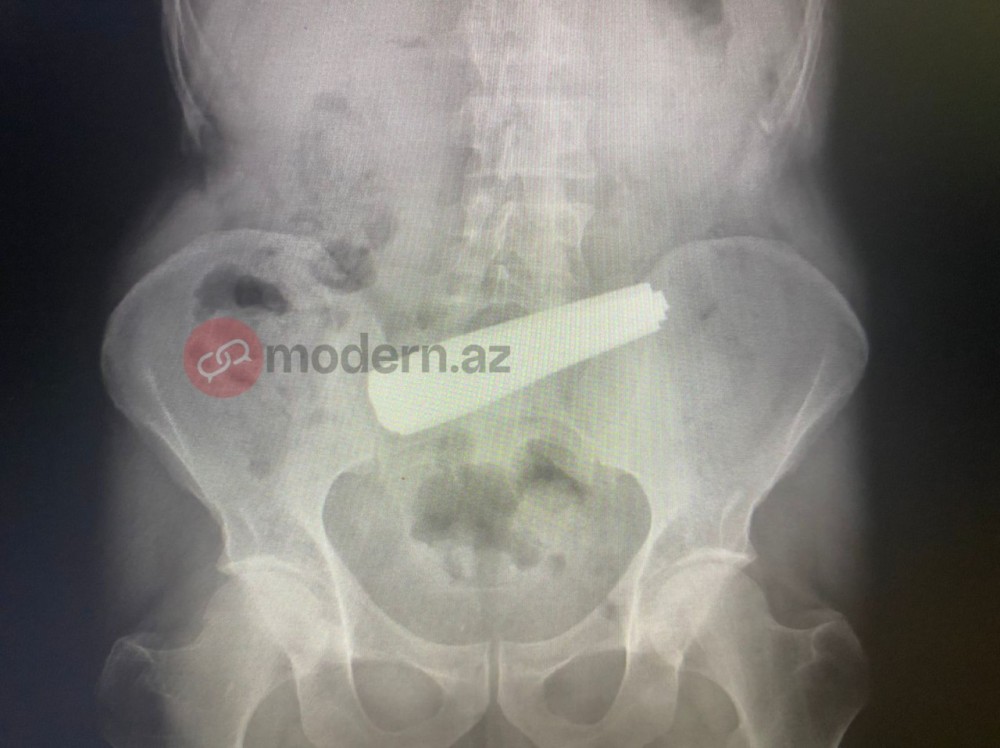

Bakıda bir nəfər 9 ədəd qaşıq udub.

Məlumata görə, xəstə 9 ədəd metal qaşığı udub. Həkimlər tərəfindən həyata keçirilən əməliyyat uğurla başa çatıb.